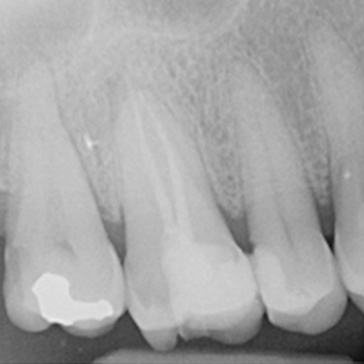

Case 1. Re-RCT of LL6